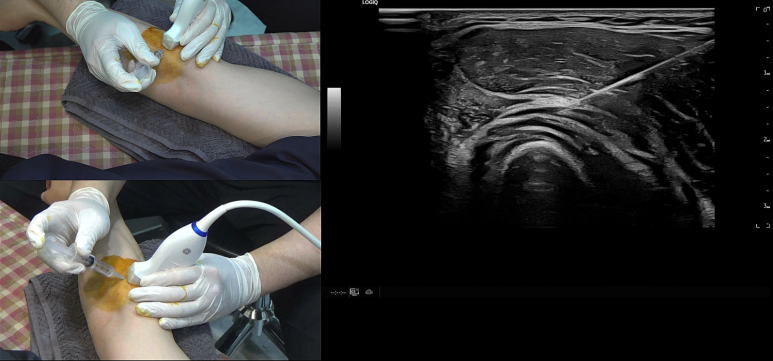

## 두 번째는 내일 바로 적용 가능한 실전적인 콘텐츠입니다. '초음파 바이블'로 불리는 교과서와 최신 지견들을 체계적으로 정리했는데, 더 놀라운 것은 이론과 임상 케이스가 결합되어 있다는 점입니다. 논문을 머리로만 이해하고 전달하는 것은 누구나 할 수 있죠. 하지만 직접 몸으로 겪은 나만의 경험을 공유하는 콘텐츠는 흔치 않습니다. 특히 양방 논문처럼 우리가 쓰지 않는 '스테로이드' 주사로 치료하는게 아니라, 우리 한의사들이 진료실에서 내일 바로 쓸 수 있는 '초음파 약침/도침'을 소개한다는 것이 가장 큰 차별점입니다. ## 세 번째는 수강으로 끝나지 않는 '올인원 교육 시스템'입니다. 소노하니 회원은 수강기간이 끝나도 내가 직접 스캔한 환자 케이스에 대해 '교차 판독 피드백'을 받을 수 있습니다. 그리고 최신 논문과 임상 케이스를 공유하는 단톡방 커뮤니티를 통해서 평생 함께 공부하고 성장할 수 있습니다. 또한 미국진단초음파 자격자들이 보수교육에서 모여서 함께 교류하고 있습니다. 저도 여러번 연자로 참여하였는데, 뛰어나신 동료 선후배님들에게 임상 케이스를 전달하기 위해 발표하는 과정 자체가 스스로 전문성을 한 단계 끌어올리는 가장 효과적인 '성장 전략'이 됩니다. > 소노하니 초음파, 빠를수록 좋다

뜬 구름 잡는 이야기가 아니라

내 눈으로 직접 확인하는 초음파

초음파 진단에 따라

눈으로 보면서 시술하는

'초음파 약침과 도침'